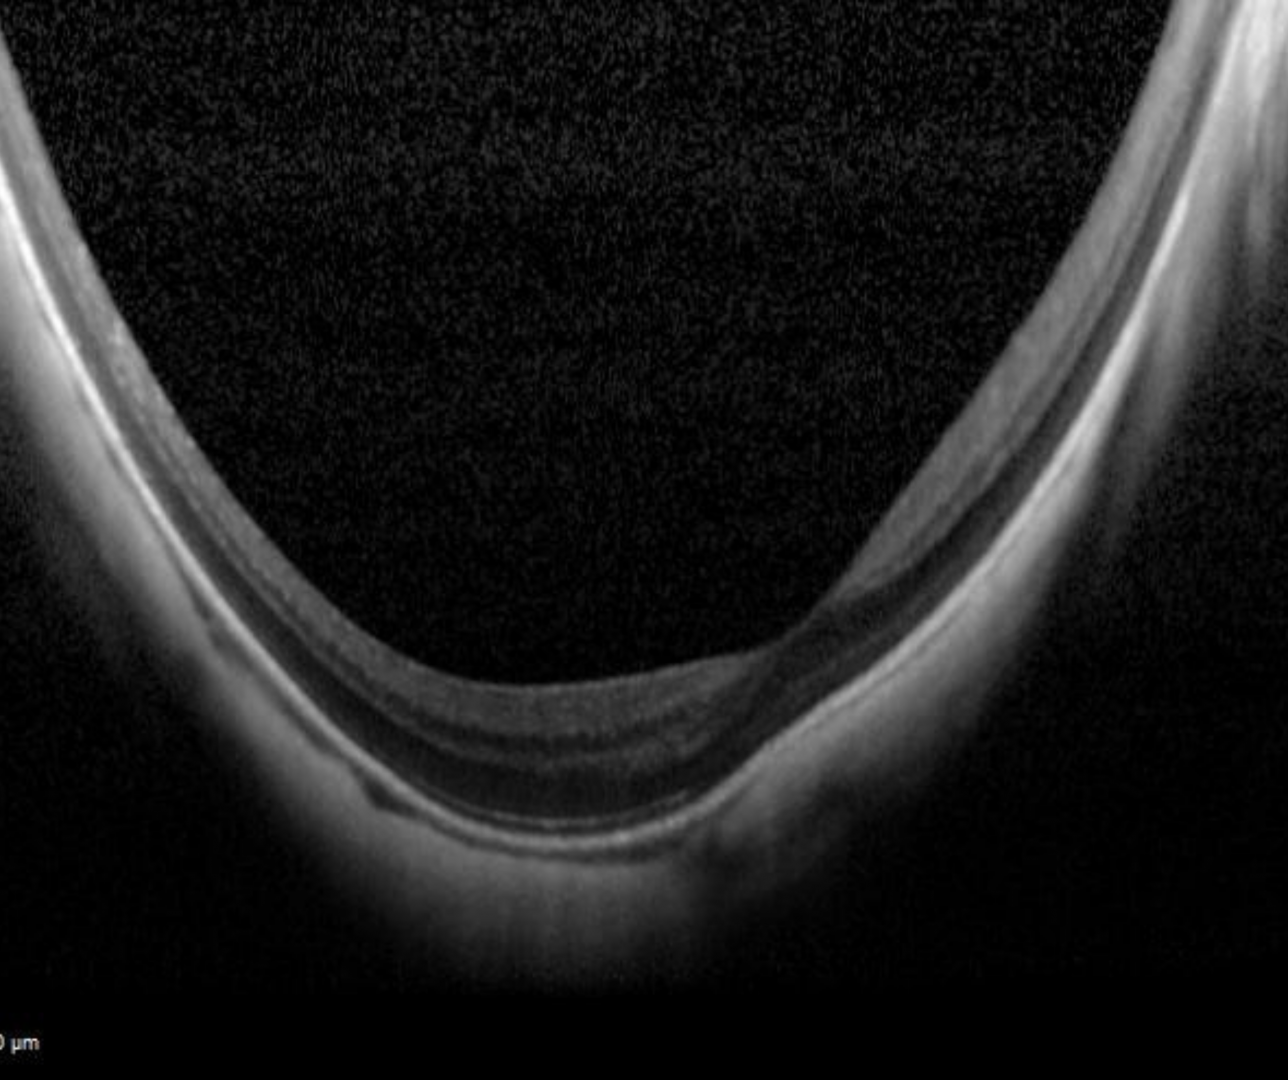

OCT imaging shows marked concavity of the sclera, choroid and retina.